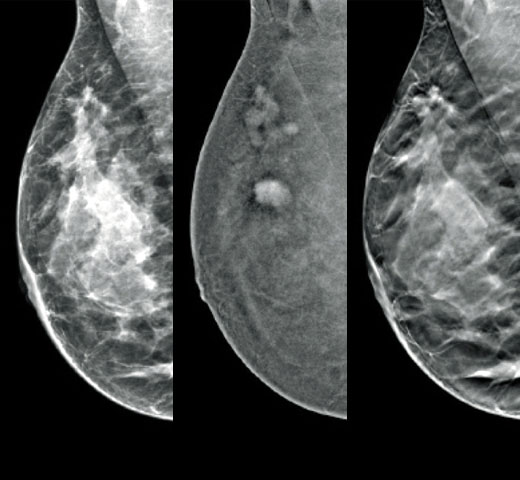

Higher breast density is known to increase a woman’s risk for breast cancer.1 The need for accurate, unbiased analysis is therefore critical. Powered by machine learning, Quantra technology software analyses both 2D™ and tomosynthesis images for distribution and texture of parenchymal tissue. It categorises breasts in four breast composition categories consistent with guidance from the American College of Radiology (ACR) BI-RADS Atlas 5th Edition.2

In addition to volume, pattern and texture of fibroglandular tissue may play just as an important role in mammographic cancer risk prediction.3-5 By analysing and categorising breast texture and pattern, our technology can deliver the accurate information you need to achieve more consistent and reliable scoring and confidently design patient-specific screening.

Quantra software’s unbiased algorithm analyse both 2D and tomosynthesis images to support your analysis by:

• Facilitating patient management protocols for supplemental imaging.